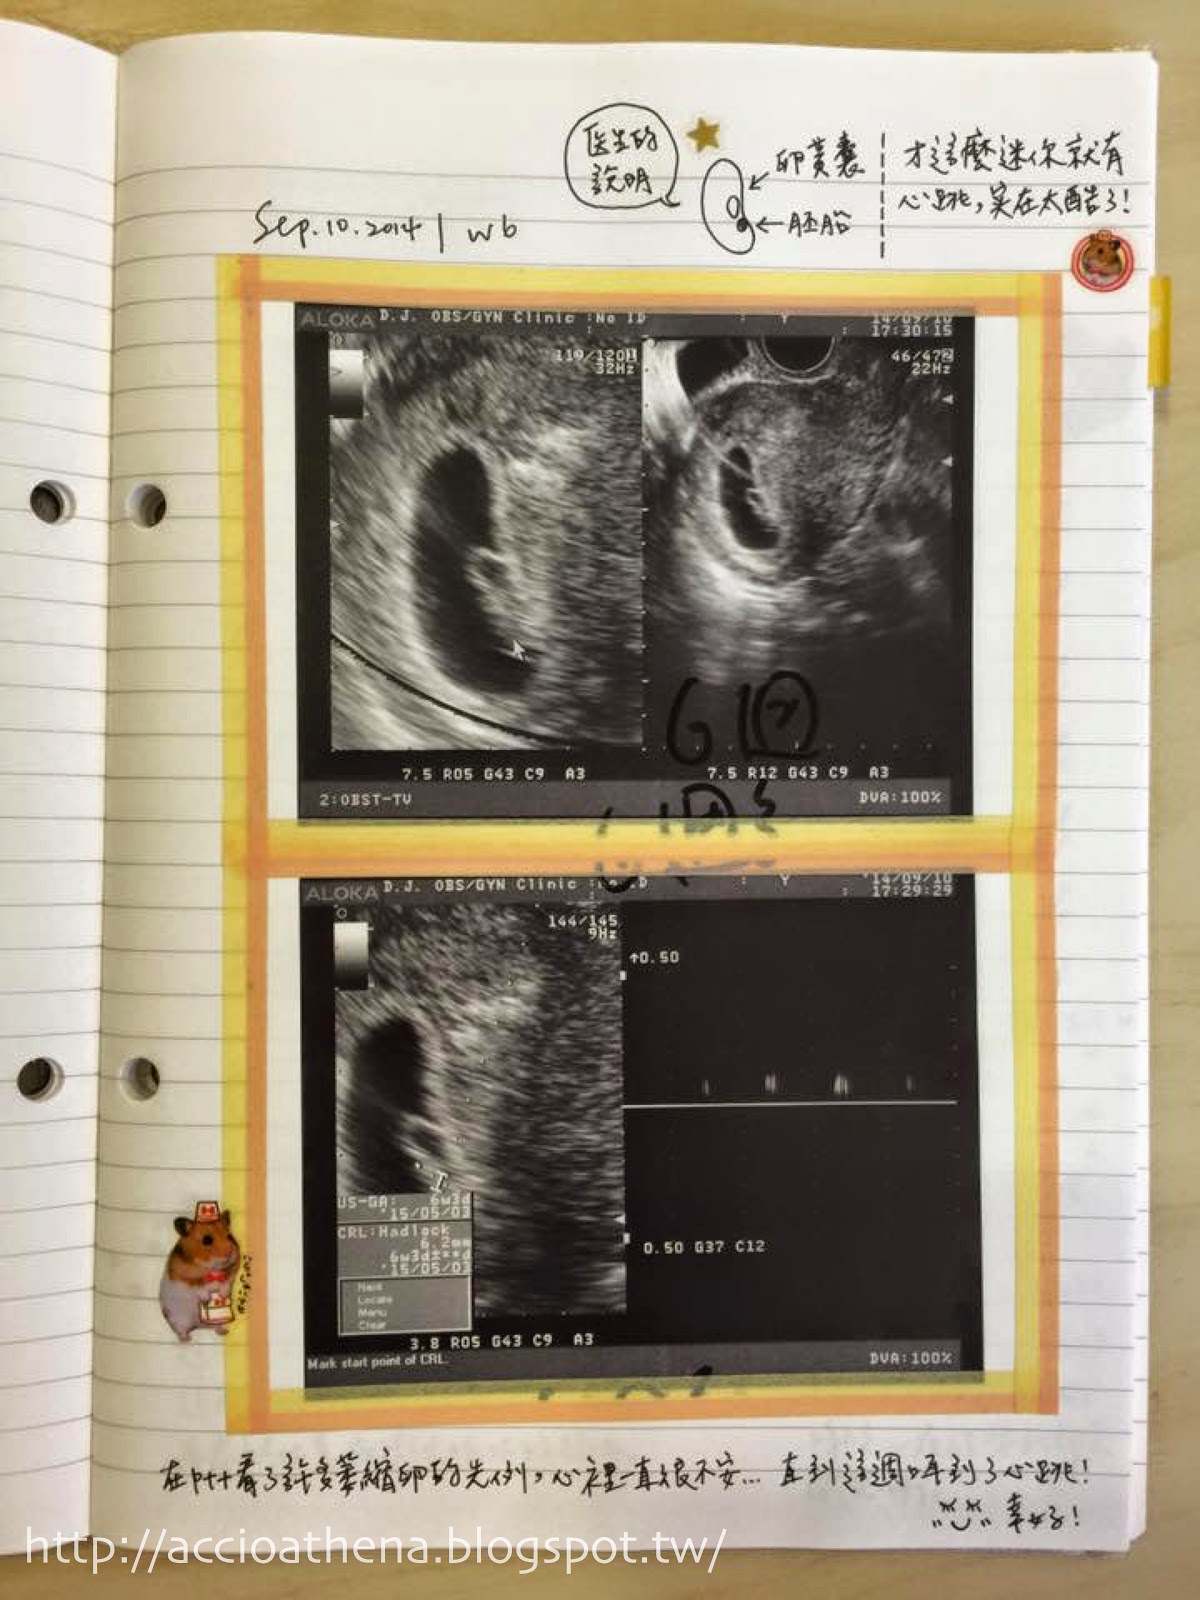

第六週,花生形狀的胚囊裡長出小小的胚胎,居然還有了微弱的心跳!

雖然還是頭暈想吐到不行,但我忍不住在診療檯上嚷嚷:哇噢天啊這真是太酷了!!!